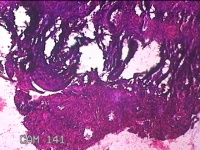

宫颈管内膜组织

性别

女

年龄

39岁

临床诊断

子宫异常出血 子宫内膜不典型增生?子宫内膜占位性病变待查 慢性宫颈炎

一般病史

阴道流血3天,增多1小时。

标本名称

大体所见

灰白暗红色不规则碎组织1.8x1.3x0.3cm一堆。

子宫颈管内膜和子宫内膜组织,没有什么大问题。